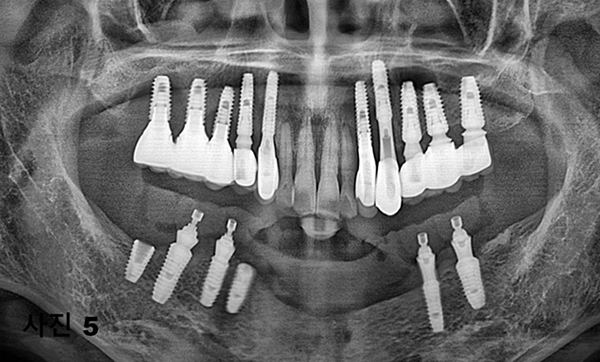

환자의 아래턱 뼈의 상태가 심한감염에 의하여 임플란트를 더 이상 심지 못하기에 양쪽 구치부위에 5개를 식립하고,

풀아치 고정성 보철물을 하여주기로 하였다. 국소마취후, (사진4)와 같이 감염된 모든 임플란트를 제거 후,

(사진5)과 같이 5개의 임플란트를 식립해 4개를 사용하여, (사진6)과 같이 본원에서 CAD/CAM을 이용하여 풀아치 임시 보철물을 제작하여

심미적,기능적인 면을 수술후 빠른 시간내에 환자분이 만족스럽게 임시치아를 만들어 주었다.